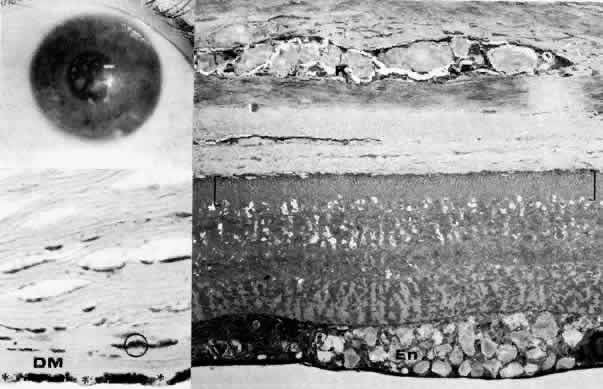

Fig. 11. Macular corneal dystrophy. Top left. Clinical appearance of cornea features diffuse haze extending to the limbus with superimposed, dense gray-white spots. Bottom left. Light photomicrograph of posterior cornea shows endothelial cells staining intensely positive for acid mucopolysaccharide. Guttate excrescences (*) of Descemet's membrane (DM) are frequent. The stroma also shows positive staining for acid mucopolysaccharide both diffusely extracellularly and intensely within keratocytes (circled) (colloidal iron × 500). Right. Transmission electron micrograph discloses typical fibrillary granular deposits within keratocytes (K), throughout the posterior layer of Descemet's membrane, and within the endothelial cells (En). The anterior banded region of Descemet's membrane (bracketed) is not affected (× 3500).

The lesions in macular corneal dystrophy stain intensely with alcian blue and colloidal iron, minimally with PAS, and not at all with Masson's trichrome. Birefringence is decreased. The lesions have been histochemically identified as an abnormal keratan sulfate-like glycosaminoglycan that accumulates extracellularly within the stroma and Descemet's membrane and intracellularly within keratocytes and endothelium.130

As would be typical of an autosomal recessively inherited condition, macular dystrophy presumably results from deficiency of a hydrolytic enzymes (sulfotransferase) and may thus be considered a localized mucopolysaccharidosis.131 The effect of altered glycosaminoglycan metabolism is evident at the cellular level; on transmission electron microscopy, keratocytes and endothelial cells exhibit distention of rough-surfaced endoplasmic reticulum cisternae. With the acridine orange technique, compensatory generalized hyperactivity of the lysosomal enzyme system has been demonstrated.132 Eventually the accumulated undigested storage products engorge the cells, and the cells ultimately degenerate or rupture. The derivation of these intracytoplasmic storage vacuoles from endoplasmic reticulum suggests that the biochemical lesion in macular dystrophy occurs at a different metabolic location than in the systemic mucopolysaccharidoses, since in the latter, storage products accumulate within lysosomelike intracytoplasmic vacuoles associated with the Golgi complex.133 Snip and associates134 were able to determine that the storage phenomenon affecting endothelium and Descemet's membrane is likely also primary, since the intracellular and extracellular lesions appear ultrastructurally comparable to those evident in the keratocytes and stroma.